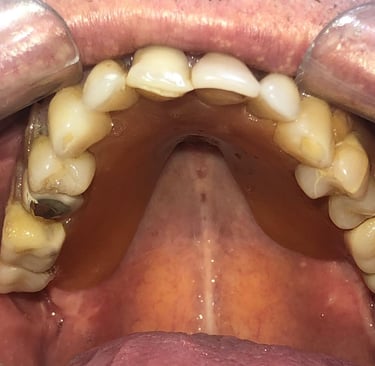

Aspecto Clínico Inicial - Fotografias originais — nenhuma contém retoques

Implantes perdidos por peri implantite - Imagens originais — nenhuma contém retoques

Implante feito por outro profissional há cerca de 5 anos desenvolveu inflamação, saída de pus e gengiva inflamada, indicando peri-implantite, uma infecção que pode comprometer o implante se não tratada.